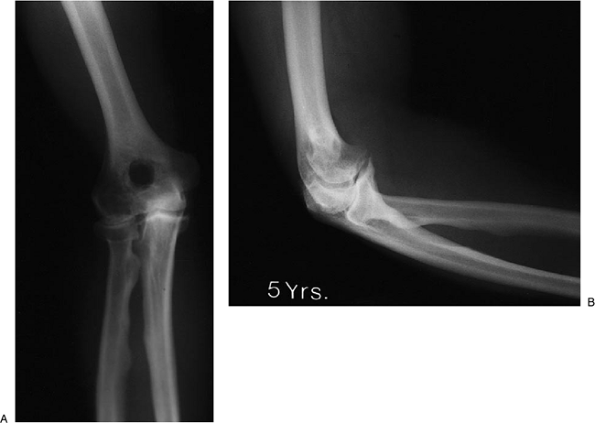

![]() |

|

Figure 20-20. A,B: Five years after removal the motion is from 20 to 130 degrees. There is no pain and the foramen osteophytes have not recurred.